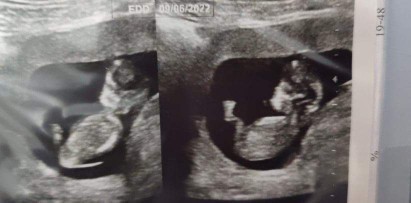

น้องเป็นแฝดตอนนี้อายุครรภ์3เดือนค่ะ